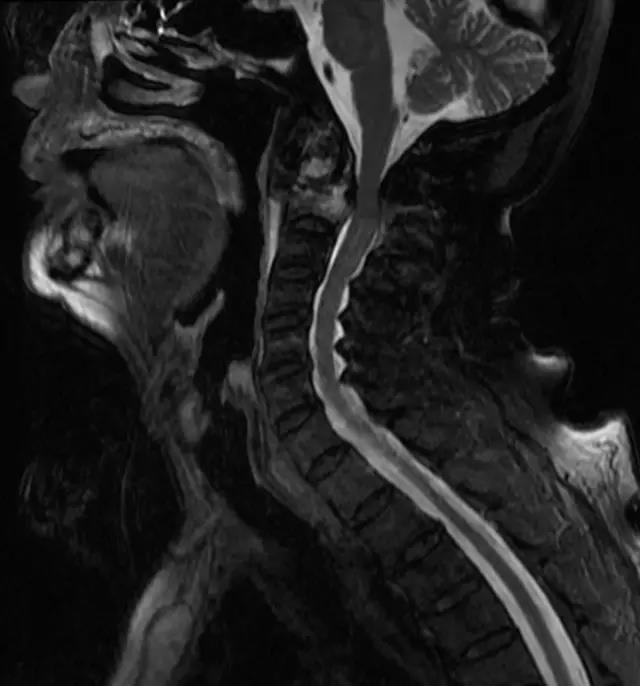

来自江苏的宣爷爷在一双儿女的陪同下,不辞辛苦来到钱列副主任的专家门诊,他双眉紧锁:“钱主任啊,我脖子疼的要命啊,两只手也麻,晚上睡也睡不着,您有办法救救我吗?”通过仔细体格检查并结合颈椎核磁共振,钱列医生发现他的颈椎椎体里长了肿瘤,已经侵蚀了两个椎体(C1、C2),考虑恶性肿瘤可能性大,如不及早手术治疗,病情会进一步恶化。然而,患者已经93岁高龄,手术和麻醉存在一定风险。但是,面对患者的诉求和愁眉不展的家属,钱列医生还是决定积极治疗:“老先生,不用担心,我们一定尽力为你诊治。”

患者入院后,脊柱外科医疗团队积极组织术前各科会诊及完善相关检查,老先生既往体健,无高血压、糖尿病等内科慢性病,术前全身检查未发现原发肿瘤病灶,全科在疑难病例讨论后,制定了最合适的手术方案。经过一系列的缜密准备,钱列副主任、劳立峰主治医师在麻醉科、手术室、重症医学科的保驾护航下,为患者实施了颈椎后路肿瘤切除减压内固定术,手术仅用时2个多小时,术中出血量不到100ml。术后症状逐渐缓解,病理提示C2恶性肿瘤,已联系肿瘤科、放疗科进一步诊治。